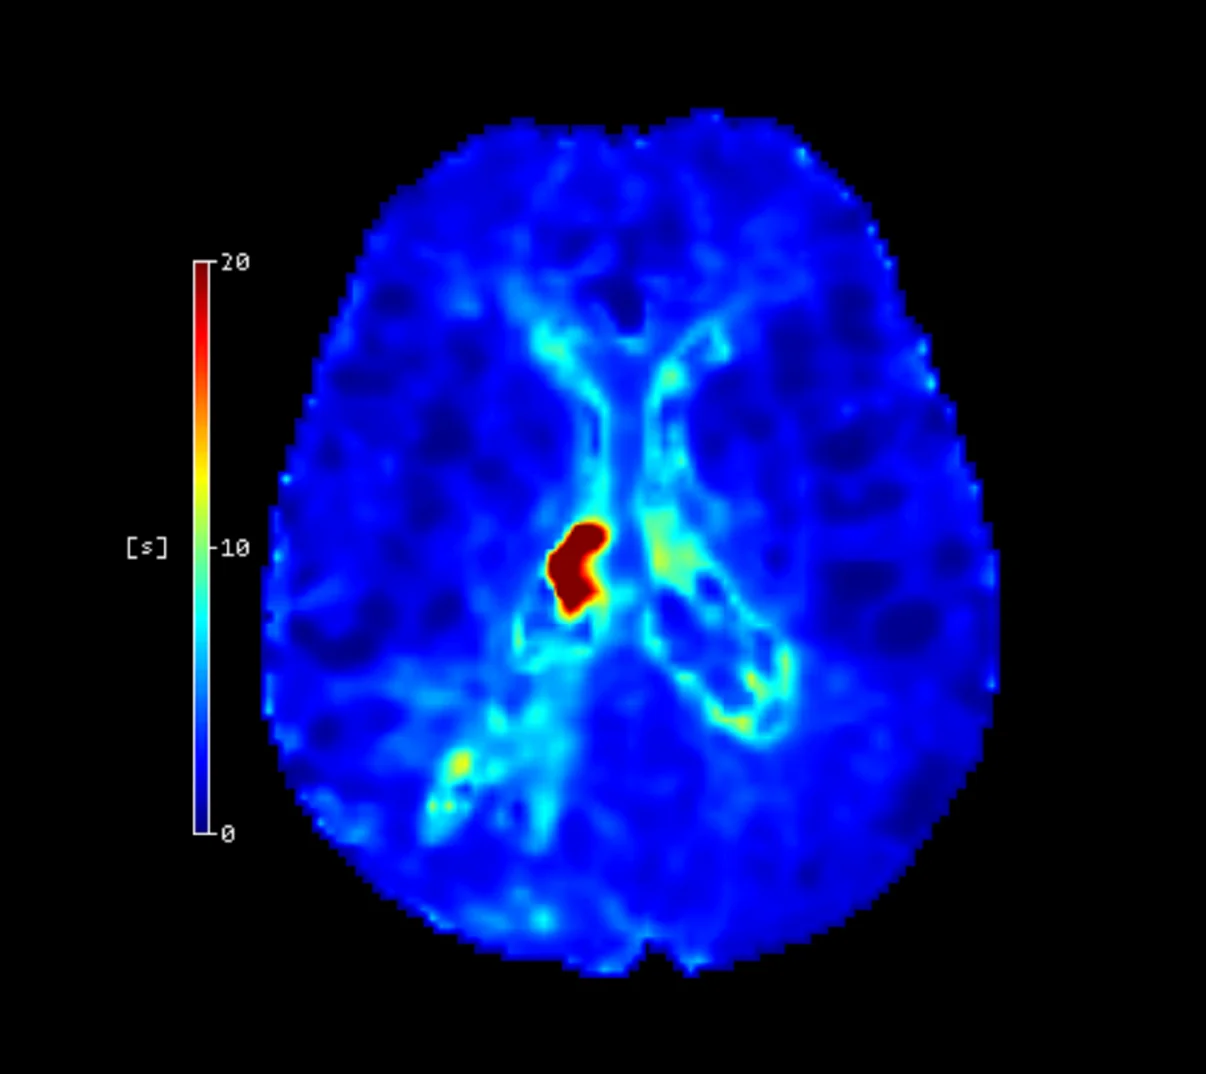

Klinik Validasyonlar

Cercare Medical Neurosuite Stroke çözümleri, hem CT hem de MR verileri ile tamamen otomatik perfüzyon analizisağlayarak klinik kararlara doğrudan katkıda bulunur. Sistem, inme çekirdek infarktı ve hipoperfüze doku hacimleriniotomatik olarak belirler ve bu sonuçlar CE ve FDA onaylı eşik tabanlı yöntemlerle veya yalnızca Avrupa’da CE işaretli yapay zeka tabanlı yöntemle elde edilebilir  .

Ayrıca, ileri biyobelirteçler olan OEF (Oxygen Extraction Fraction) ve CMRO₂ (Cerebral Metabolic Rate of Oxygen) haritaları, beynin oksijen metabolizması hakkında derinlemesine bilgi sunar. 2024 yılında yayımlanan Bani-Sadr ve ark. çalışmasında, OEF ve CMRO₂ değerlerinin trombektomi sonrası doku iyileşmesini öngörmede güvenilir belirteçler olduğu gösterilmiştir .

Tmax ve CBF eşik değerleri ile mismatch analizi, kurtarılabilir doku (penumbra) ile geri dönüşsüz infarkt alanının ayrımını yüksek doğrulukla yapar. Klinik validasyon çalışmaları, bu metodun tedavi penceresinin genişletilmesinde kritik rol oynadığını göstermektedir .

Cercare Neurosuite aynı zamanda ASPECTS skorlama, büyük damar tıkanıklığı (LVO) tespiti ve intrakraniyal hemoraji (ICH) saptama modülleri ile genişletilebilir. Bu eklemeler özellikle gelişmiş paketlerde bulunur ve klinik karar desteğini güçlendirir.